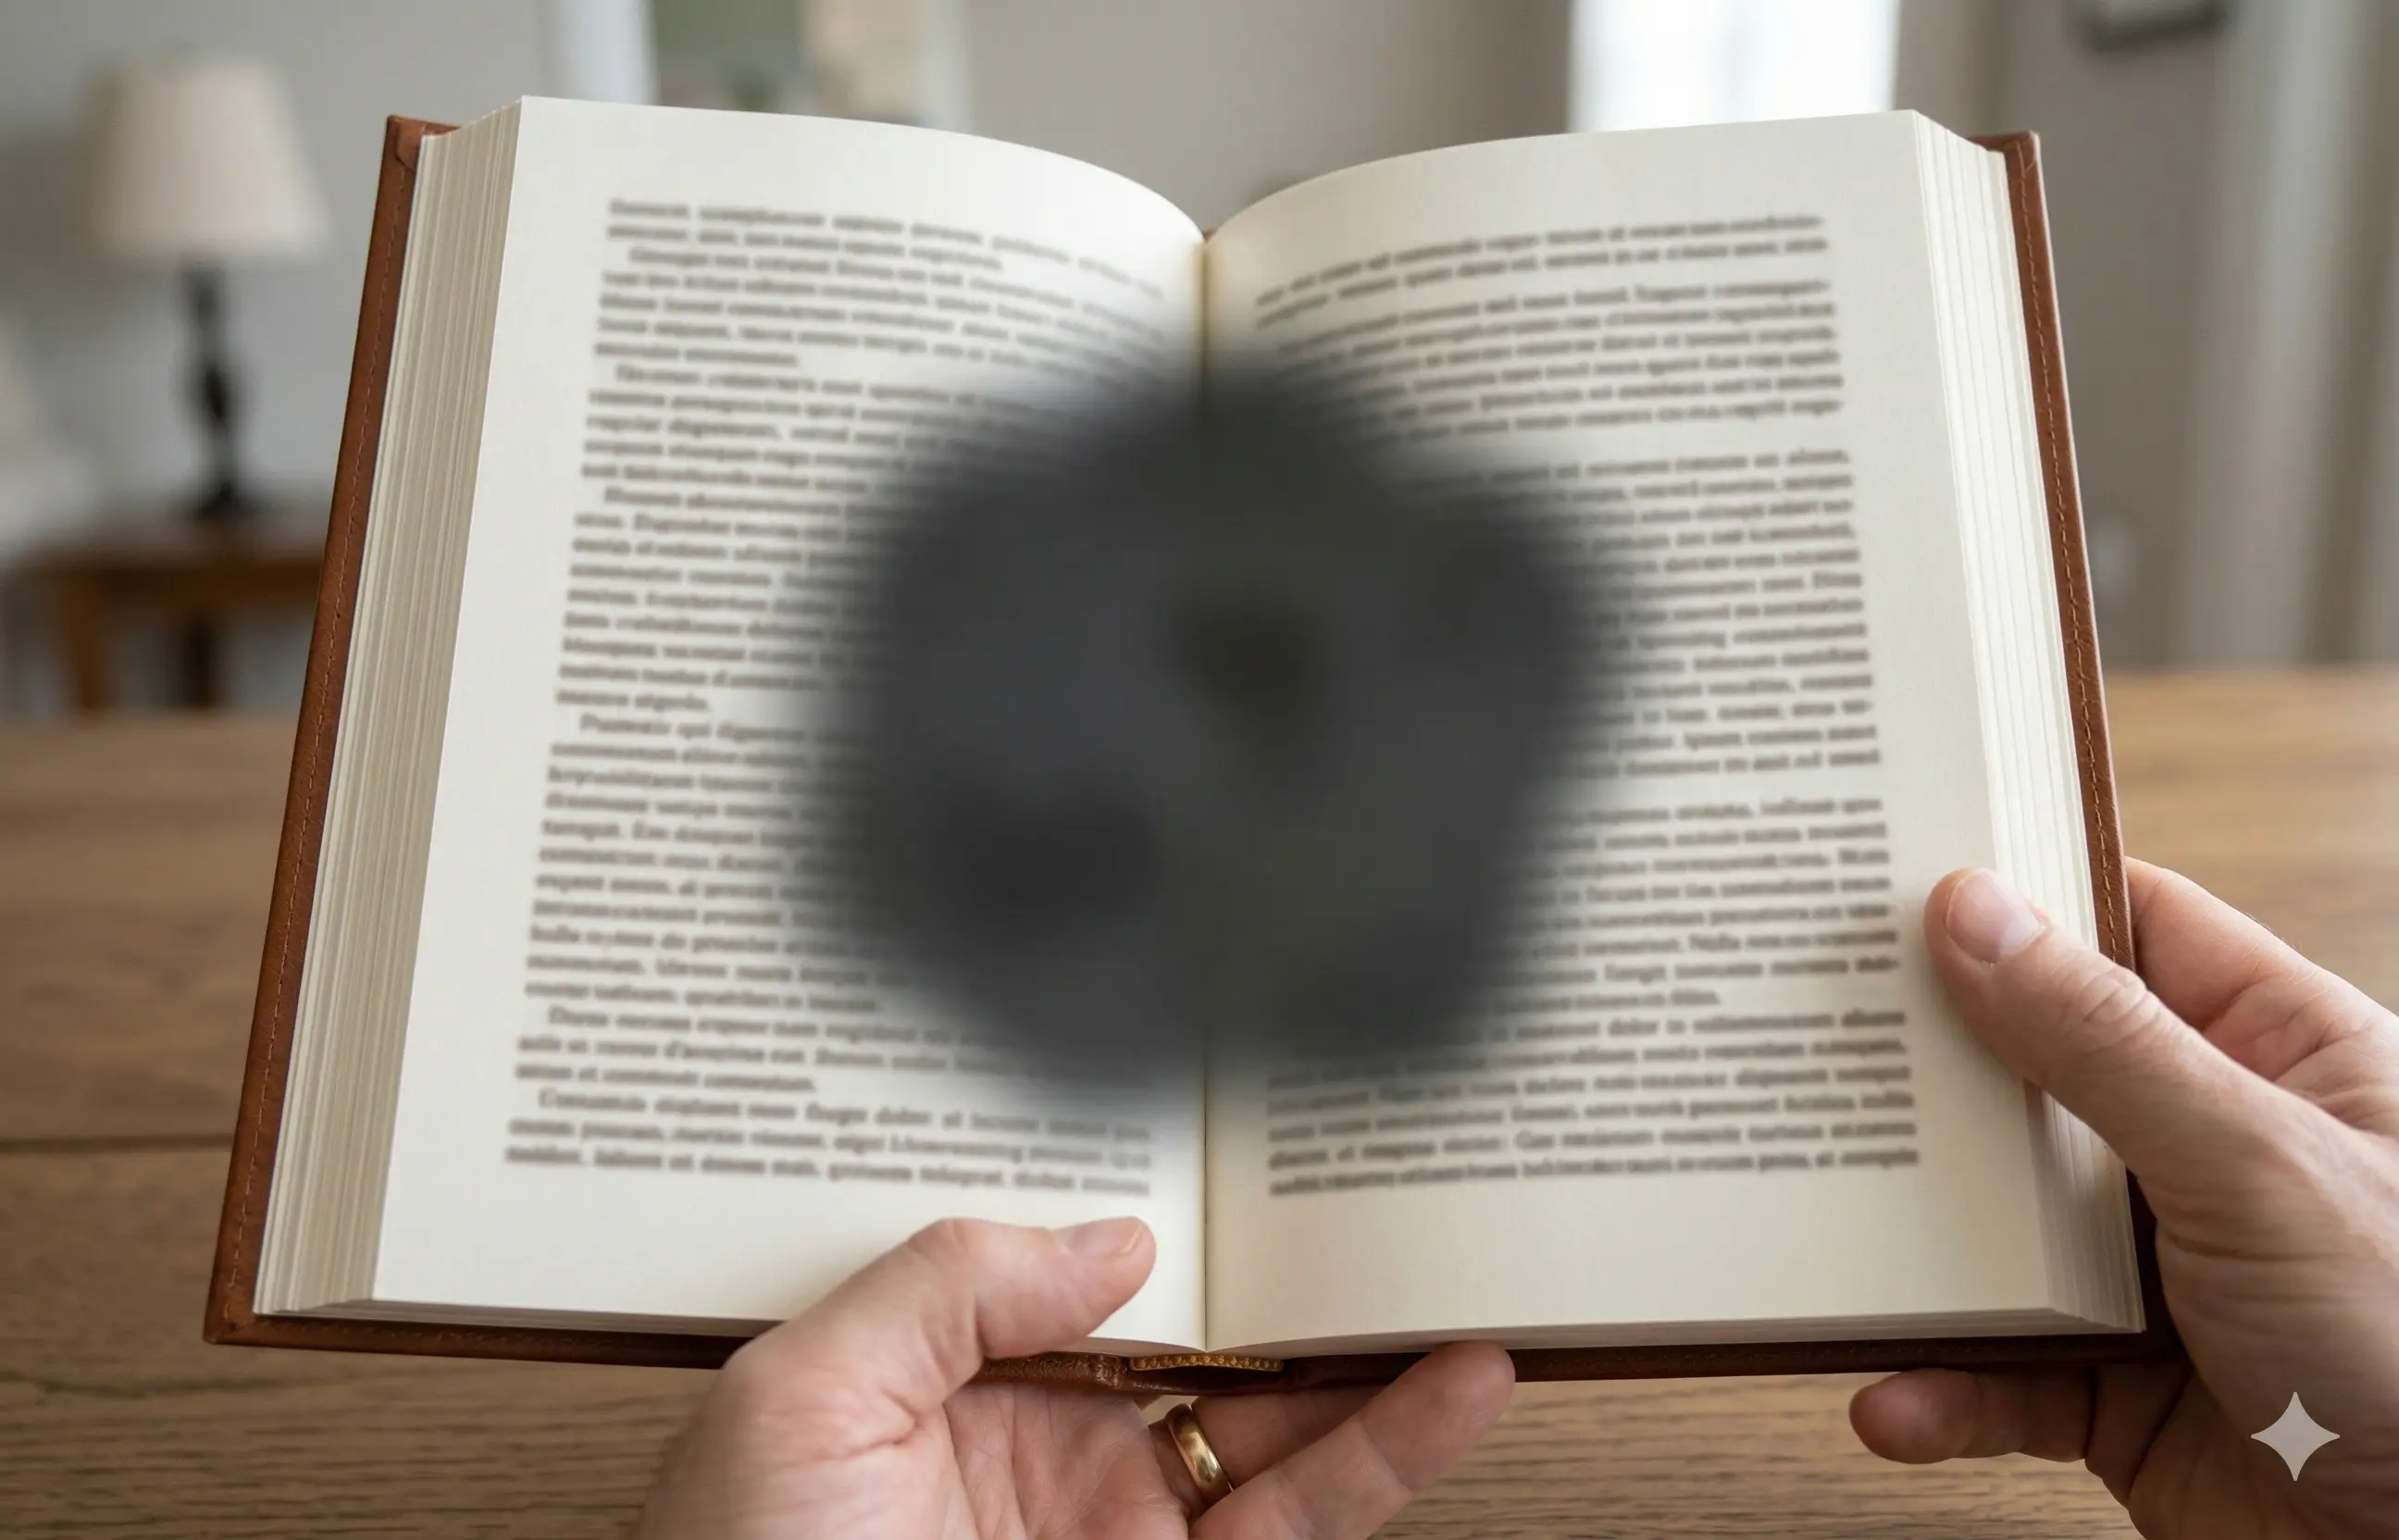

AMD does not have to be a life sentence of eye injections. Discover the cellular root cause and how to naturally reactivate macular repair.

AMD does not have to be a life sentence of eye injections. Discover the cellular root cause and how to naturally reactivate macular repair.

Those dark spots are not just a harmless annoyance. They are a primary early warning sign of progressing retinal damage.